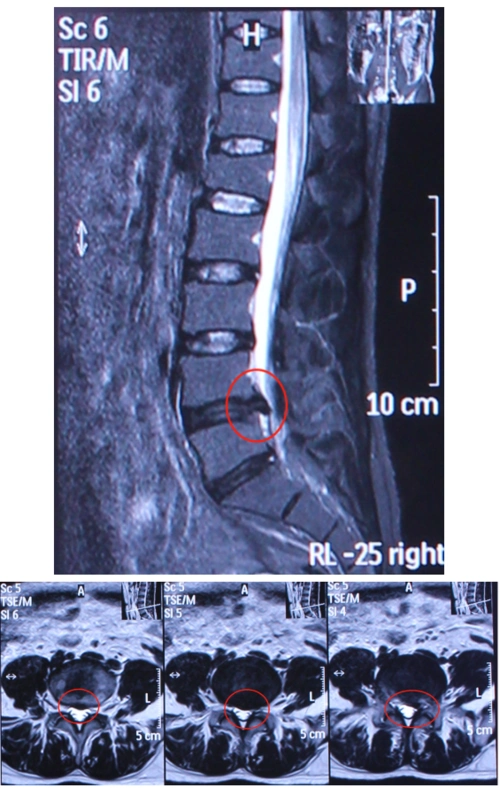

腰椎间盘突出 - 好大夫在线